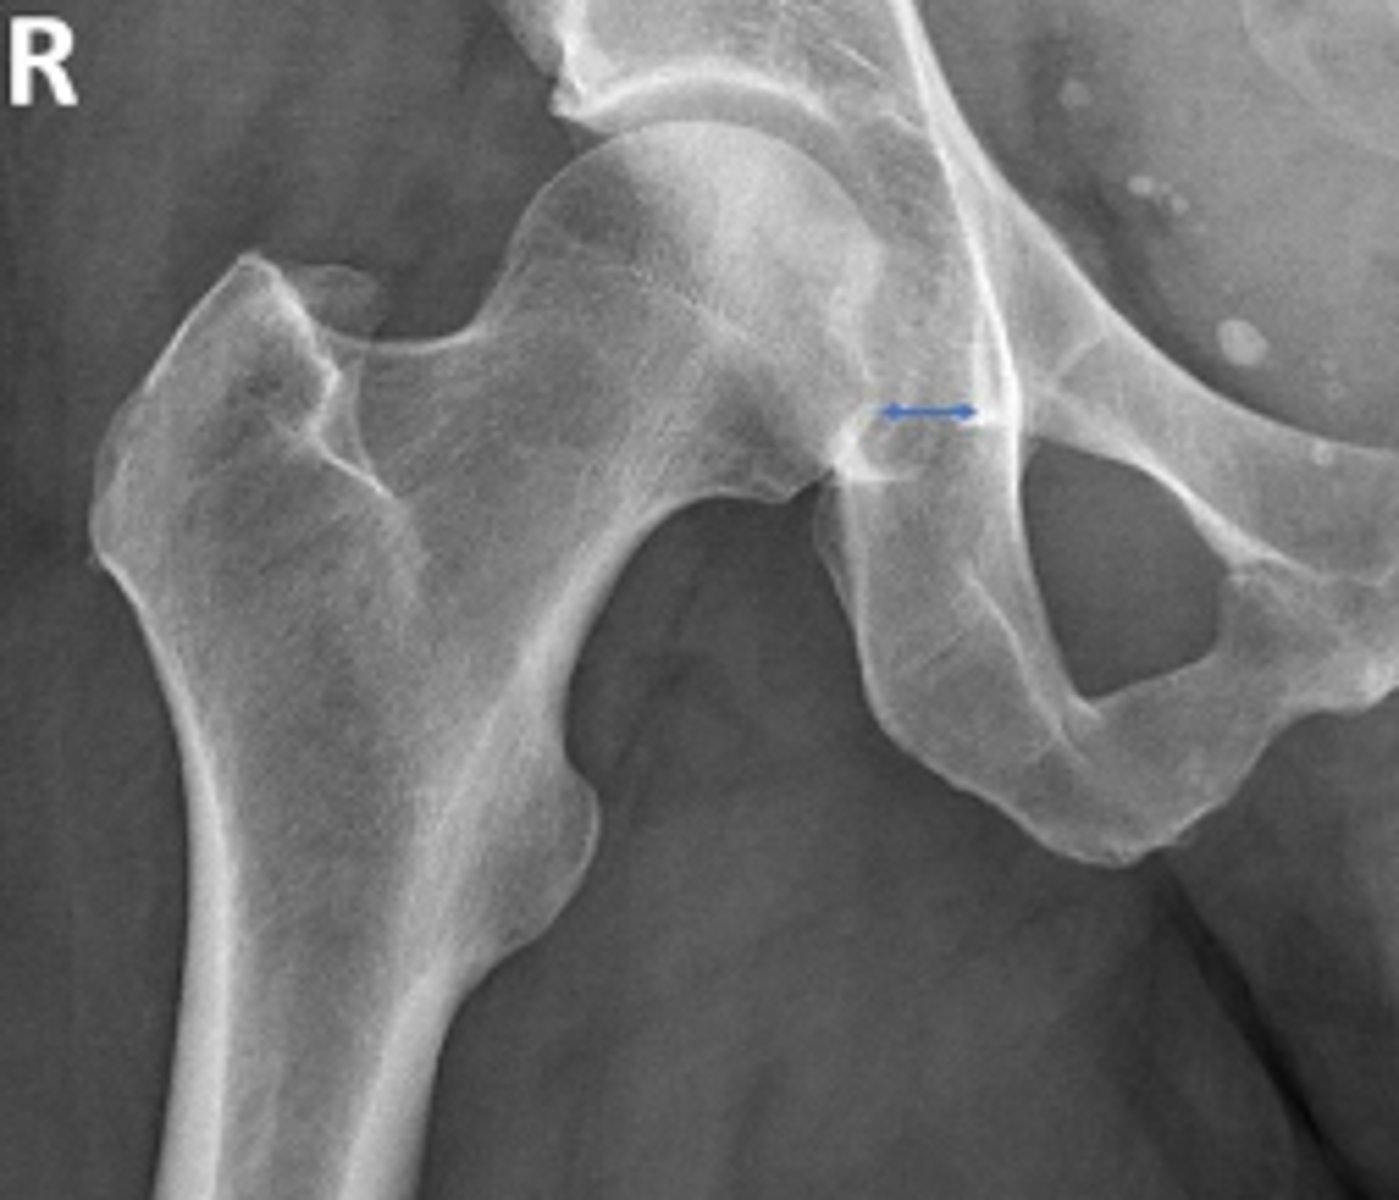

Hip joint space width

What is the name of the assessment?

Superior joint space is 3-6mm

Axial joint space is 3-7mm

Medial joint space is 4-13mm

What is the normal range for this assessment?

Superior joint space-> The measurement between the most convex superior aspect of the femoral head and the adjacent acetabulum

Axial joint space -> The measurement between the

femoral head and the acetabulum lateral to the

acetabular notch

Medial Joint space -> The measurement between the most medial margin of the femoral head and the adjacent pelvic teardrop

What are the osseous landmarks for this assessment?

Yes

Are the measurements within normal limits?

Degenerative joint disease

Name 1 condition that may result in a measurement of <3mm for the superior joint space?

AP pelvis and AP hip views

Name 2 radiographic views for this assessment?